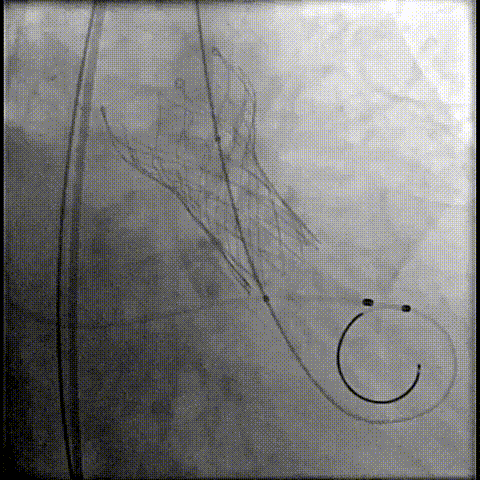

主动脉根部造影

20球囊预扩

器械过弓柔顺

初始定位